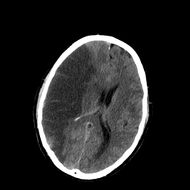

CT scan showing an intracerebral hemorrhage.

سكتة نتيجة نزيف في المخ:

ويعني تجمع الدم في أي مكان ضمن الجمجمة ويظهر في صورة صداع ويكون نتيجة كدمة بالرأس

أو نزيف داخل المخ Intracerebral haemorrhage